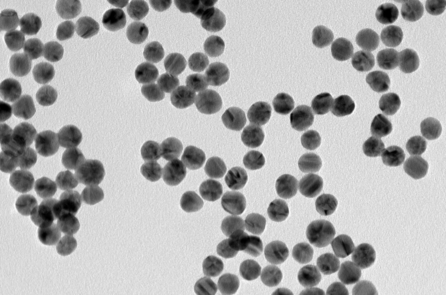

Một vài ngày sau, [tôi thấy] một viên sỏi nhỏ màu đen xuất hiện trong bộ lọc toilet trong lúc đi tiểu. Thành phần hóa học của mảnh sạn này chứa calcium phosphate và oxalate. Kích thước của viên sỏi ít có liên quan đến mức độ đau. Nguyên nhân của cơn đau là do sự co thắt dữ dội của niệu quản – một ống dẫn nhỏ dẫn nước tiểu từ thận xuống bàng quang. Một khi viên sỏi lọt vào không gian rộng ở bàng quang và niệu đạo, nó sẽ được thải ra ngoài một cách dễ dàng [mà ít gây đau đớn]. Những kẻ thù bé nhỏ này cứ lại xuất hiện để làm phiền tôi mỗi 3-5 năm, luôn luôn xuất hiện tại những thời điểm và địa điểm vô cùng bất tiện.

Một bài đánh giá Cochrane về công dụng của muối citrate trong dự phòng sỏi thận ở người trưởng thành có phần giới thiệu rõ ràng như sau: “Sỏi thận ảnh hưởng đến mọi người trên toàn thế giới và có tỷ lệ tái phát cao, ngay cả khi đã điều trị. Việc tái phát đặc biệt thường thấy với những người có nồng độ citrate niệu thấp. Những người này có tỷ lệ mắc sỏi calcium phosphate and calcium oxalate cao. Liệu pháp citrate đường uống làm tăng nồng độ citrate niệu, sau đó citrate niệu liên kết với calcium và ức chế sự kết tinh, do đó làm giảm sự hình thành sỏi. Mặc dù liệu pháp citrate đường uống được sử dụng rộng rãi để phòng ngừa và điều trị sỏi calcium oxalate, nhưng bằng chứng hiệu quả lâm sàng vẫn chưa hoàn toàn chắc chắn.”